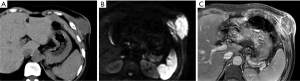

Liposarcomas

Liposarcomas are the second most common soft tissue sarcomas, accounting for 10–35% of all soft tissue sarcomas (13). Liposarcomas show the most striking diversity in pathological and biological behavior and can be categorized into several subtypes, including dedifferentiated, myxoid, pleomorphic, and mixed (23). The imaging findings of liposarcomas are frequently distinct. On CT and MRI, focal or diffuse areas of fat associated with nonlipomatous components are commonly detected, and the diagnosis can be easily determined in these cases. However, the diagnosis is not achievable in other cases without fatty tissue in the lesions (Figure 3). MRI is useful for distinguishing well-differentiated from poorly differentiated liposarcomas (11).